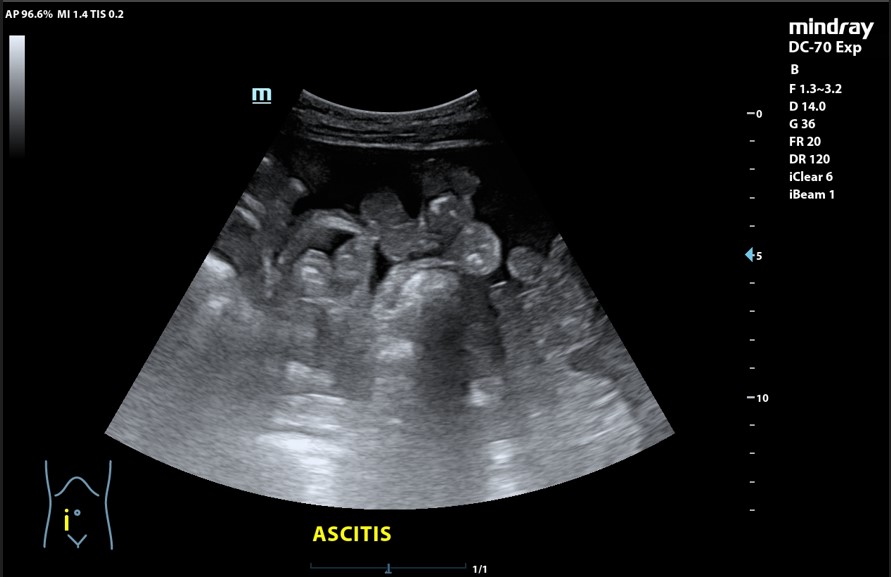

Presencia de 2 masas pélvicas bien delimitadas heterogéneas que captan Doppler, una de 5 cm de diámetro y otra ovalada de 10 cm de longitud. Líquido ascítico peritoneal, que también se observa alrededor del bazo y en espacio de Morrison. Derrame pleural derecho.